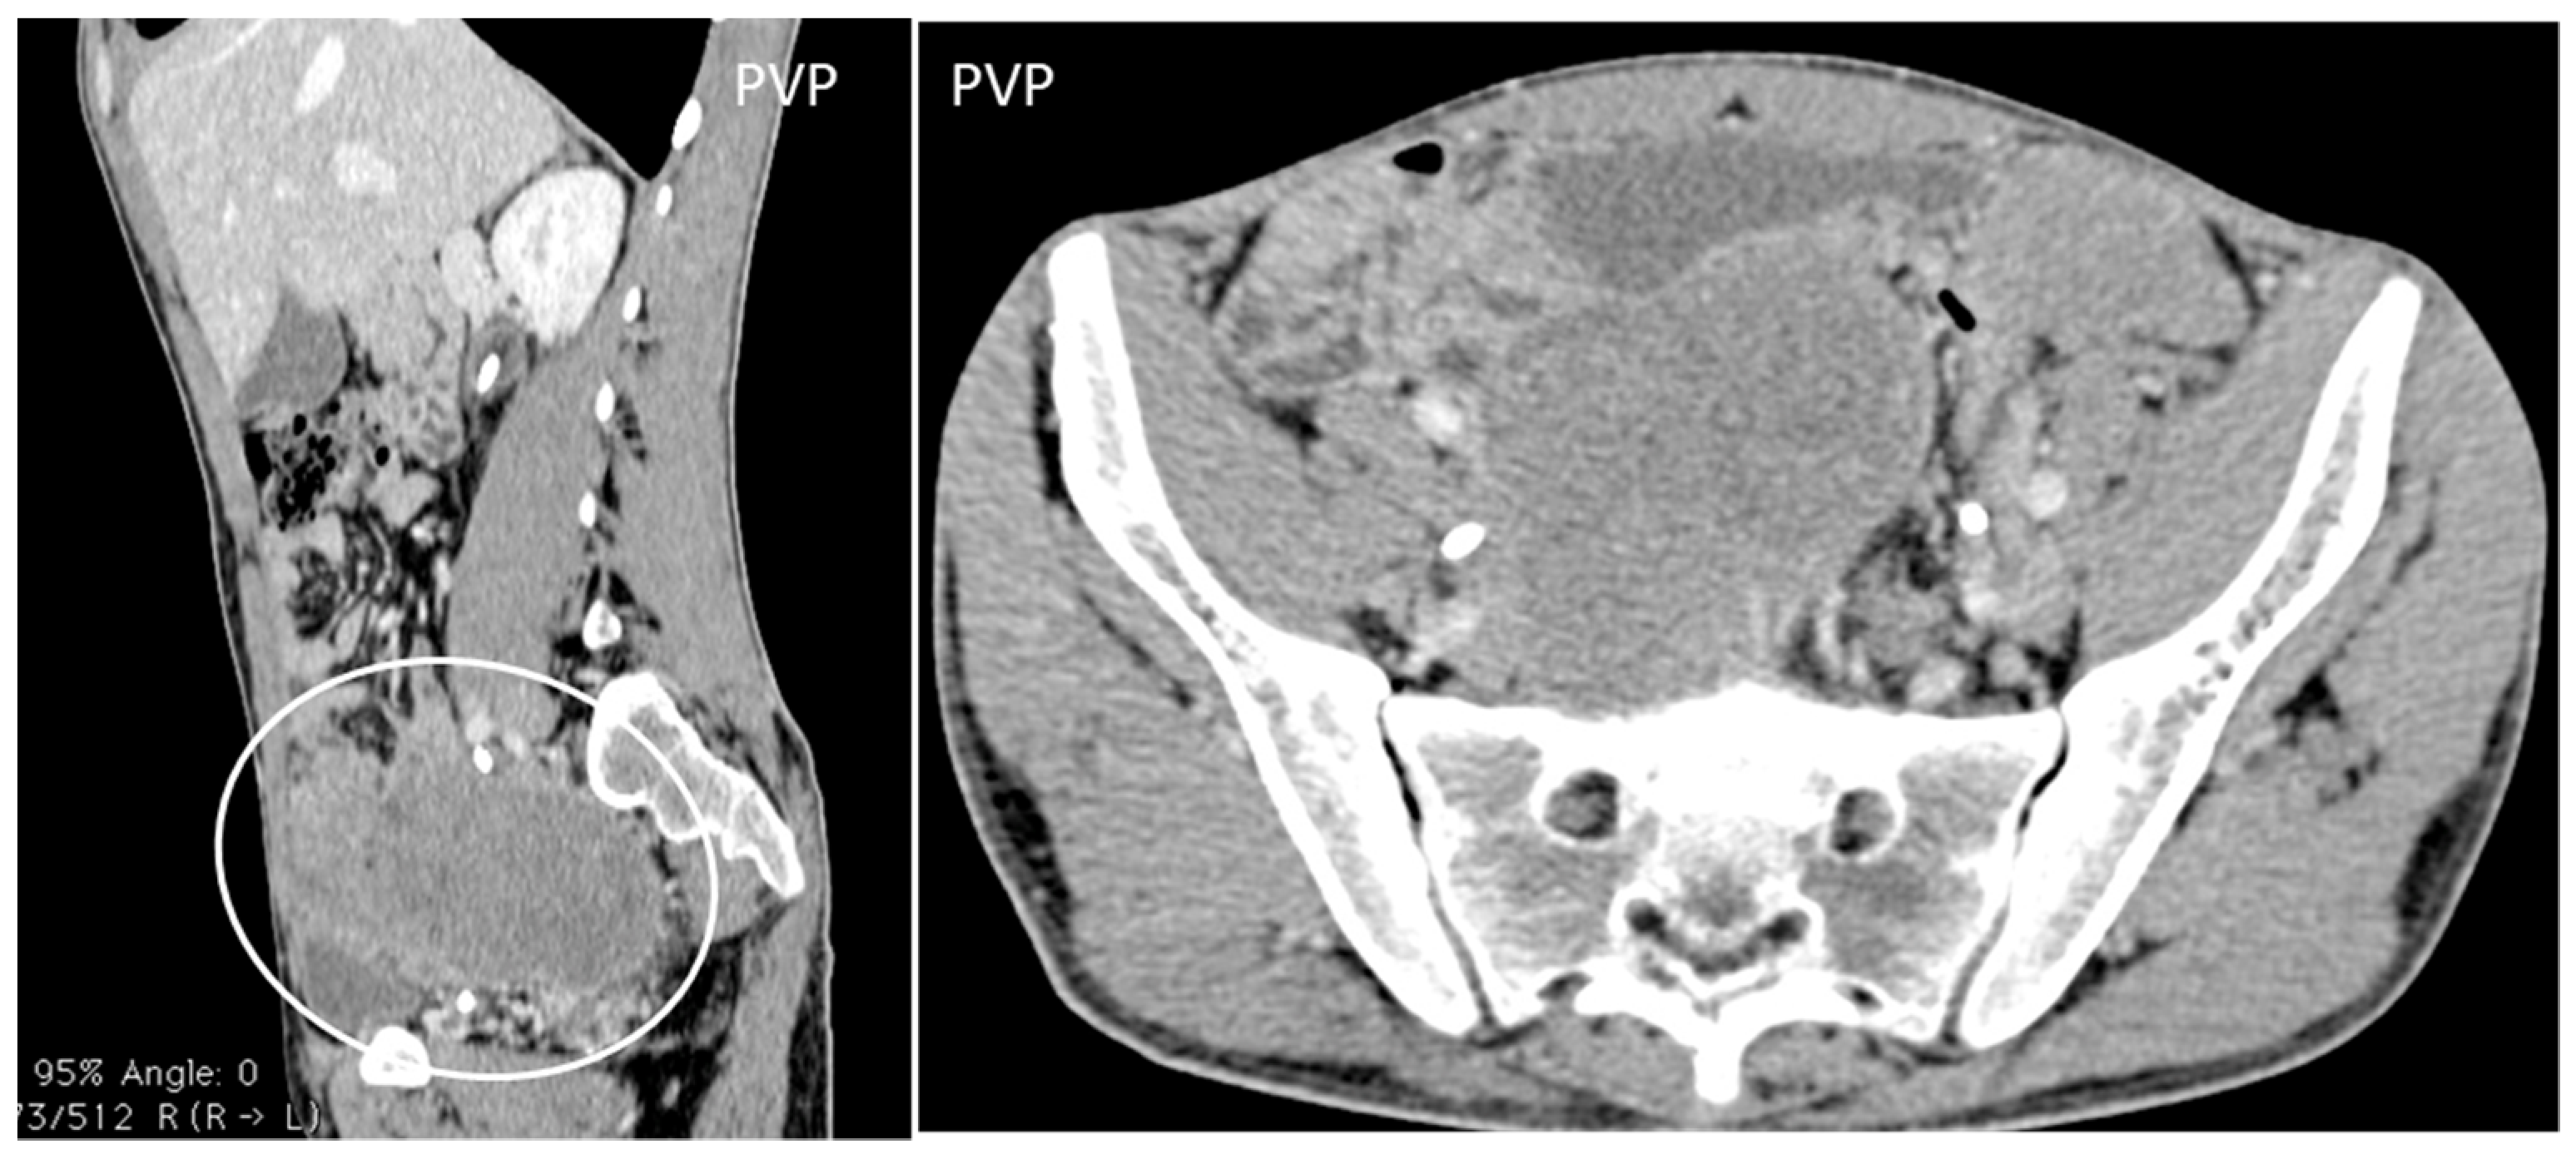

- Desmoplastic Small Round Cell Tumor (DSRCT): rare, highly aggressive sarcoma of adolescents, which primarily involves the serosal surfaces of the abdominal cavity infiltrating the abdominal wall [30,31,32]. Classic findings include bulky multiple, hypoattenuating, soft-tissue masses, with omental, serosal, and rectovesical involvement [31,32] and typical punctate or amorphous calcifications [32]. Modest heterogeneous enhancement is seen on arterial phase, without prolonged enhancement or portal washout [31,32] (Figure 10). On MR, DSRCTs are heterogeneously iso- to-hypointense on T1-w images, with hyperintense foci due to intratumoral hemorrhage [32].